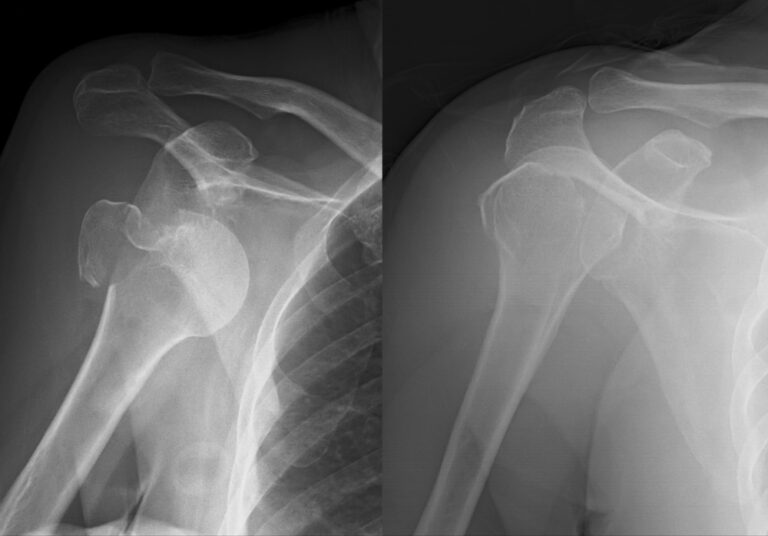

A luxação do ombro ocorre quando a cabeça do úmero, osso do braço, é deslocada de sua posição normal, que é dentro da cavidade glenoide da escápula, osso que forma o ombro. A luxação pode ser classificada em anterior (mais comum), posterior ou inferior, dependendo da direção em que o úmero se desloca em relação à escápula.

É importante buscar atendimento médico imediatamente se você suspeitar de uma luxação de ombro, pois pode levar a complicações graves, como lesões nervosas ou de vasos sanguíneos. Um médico pode realizar exames físicos e radiológicos para diagnosticar a lesão e recomendar o tratamento adequado.